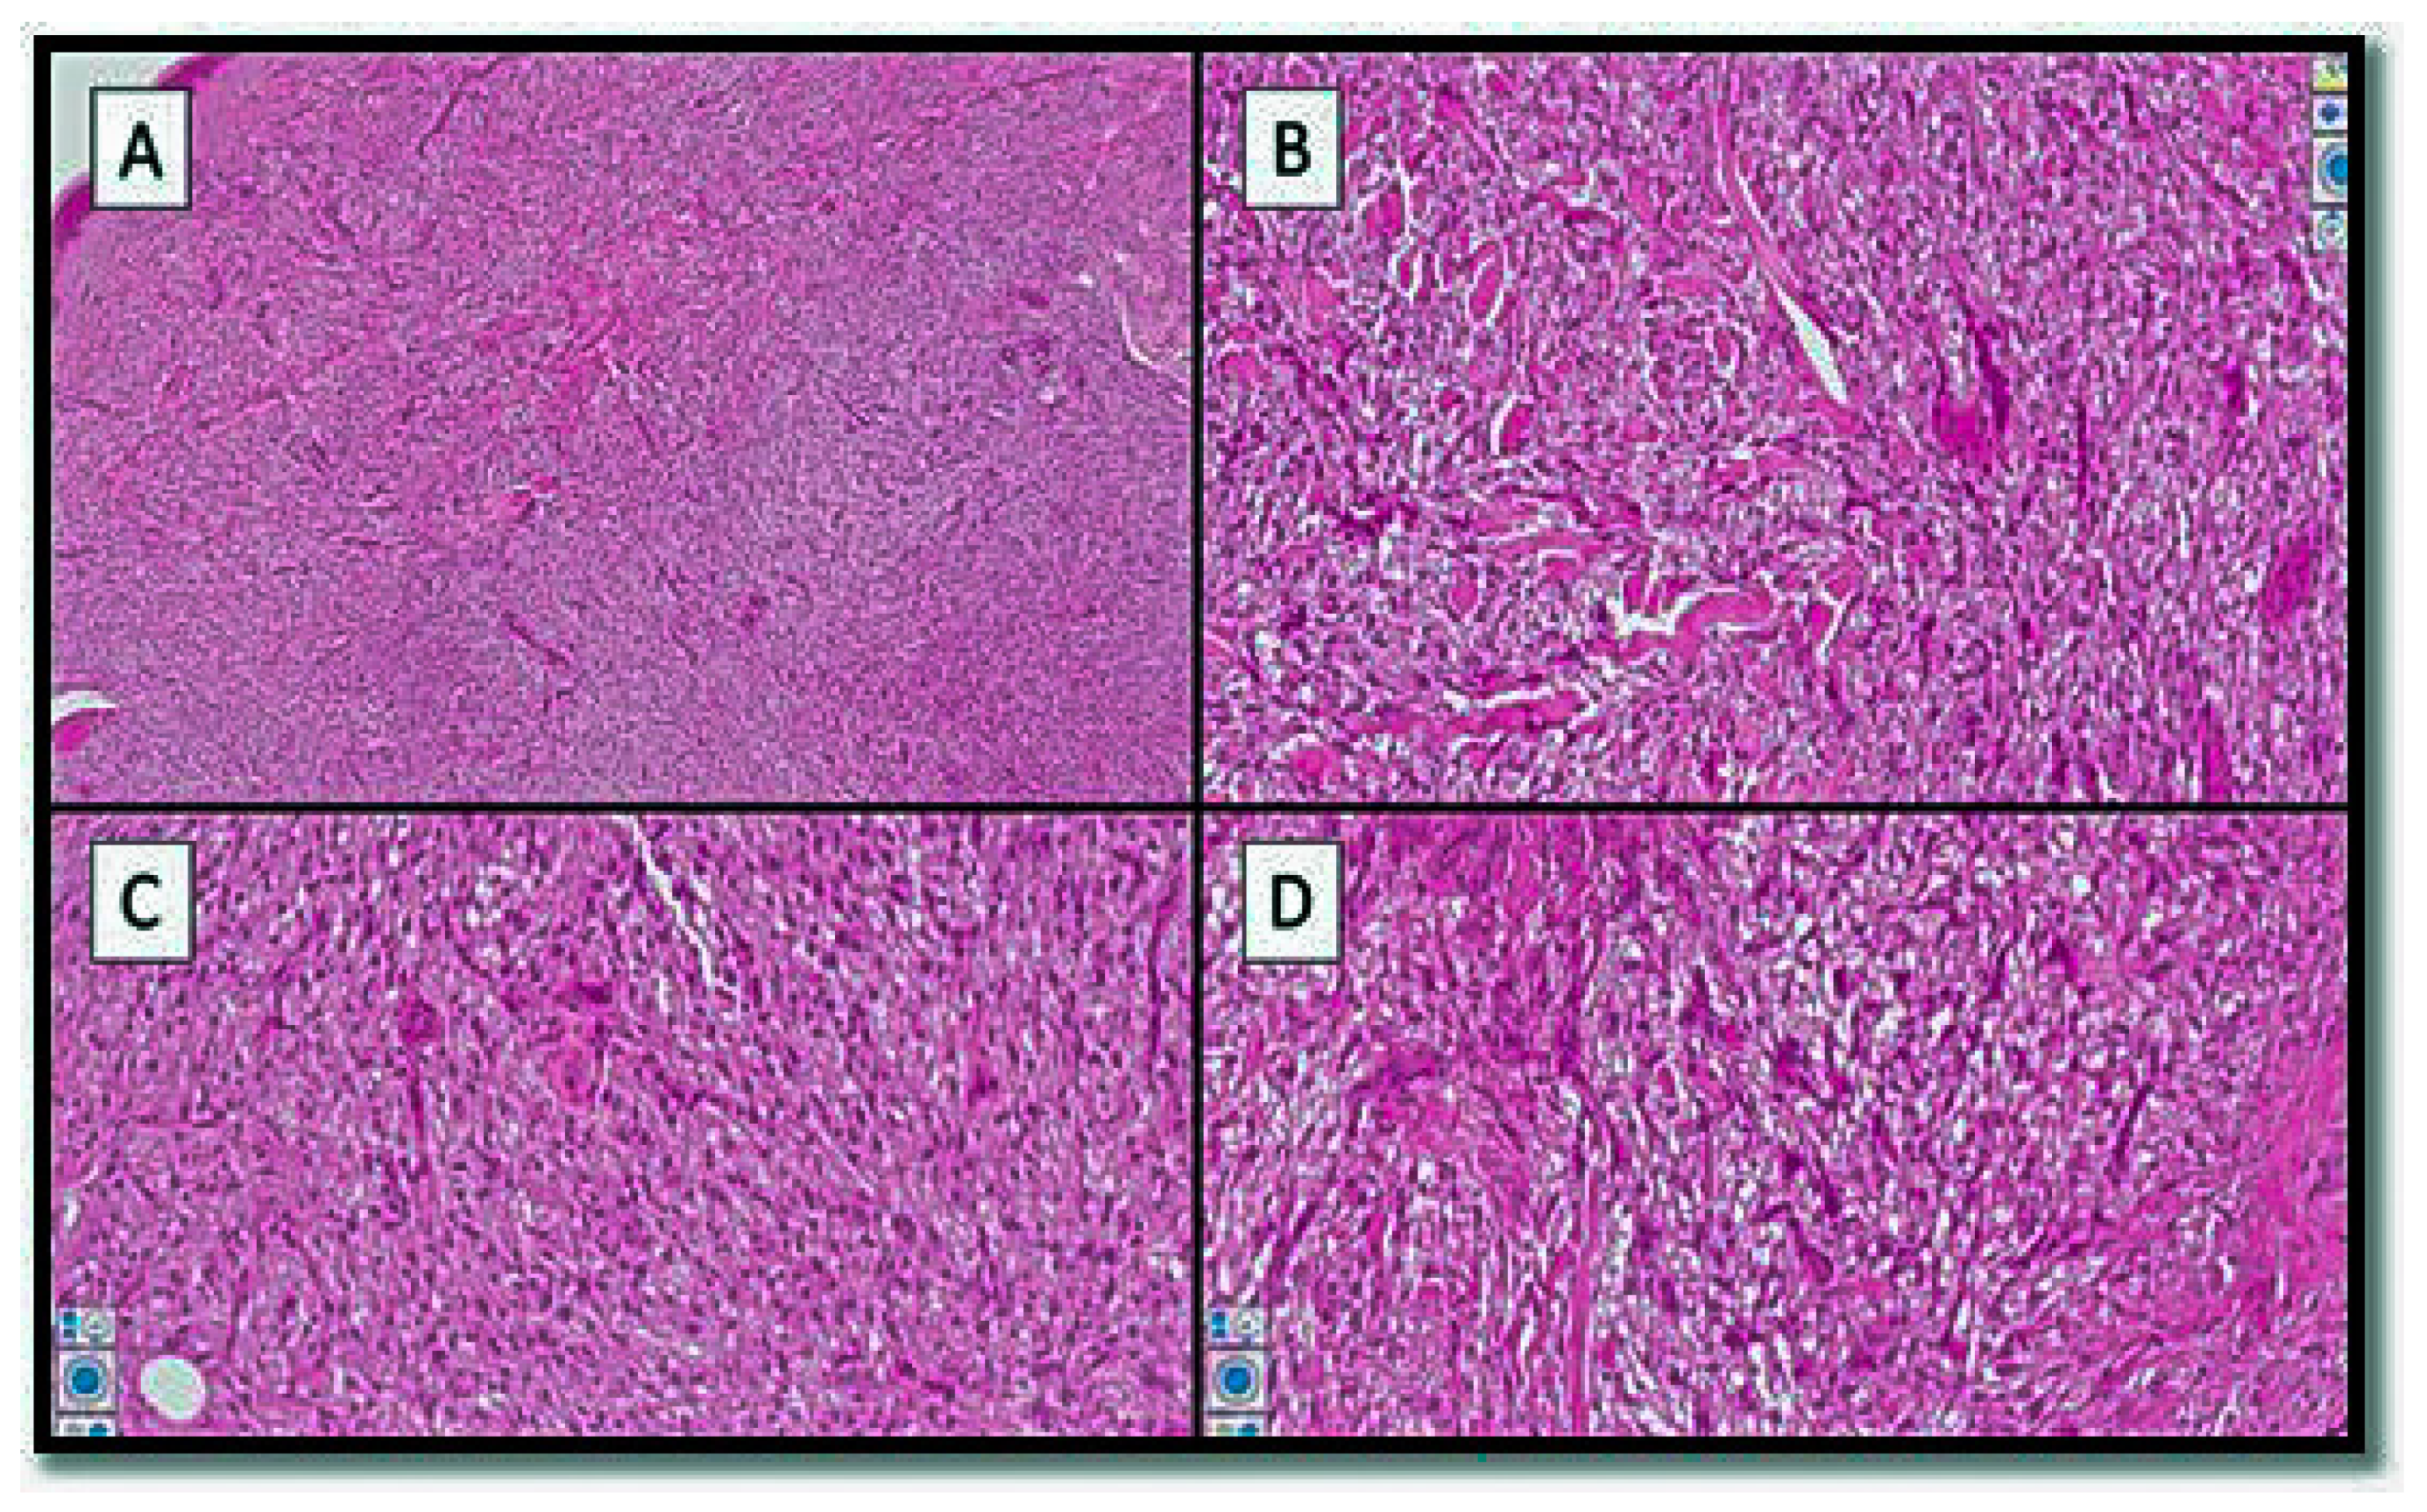

3. Results